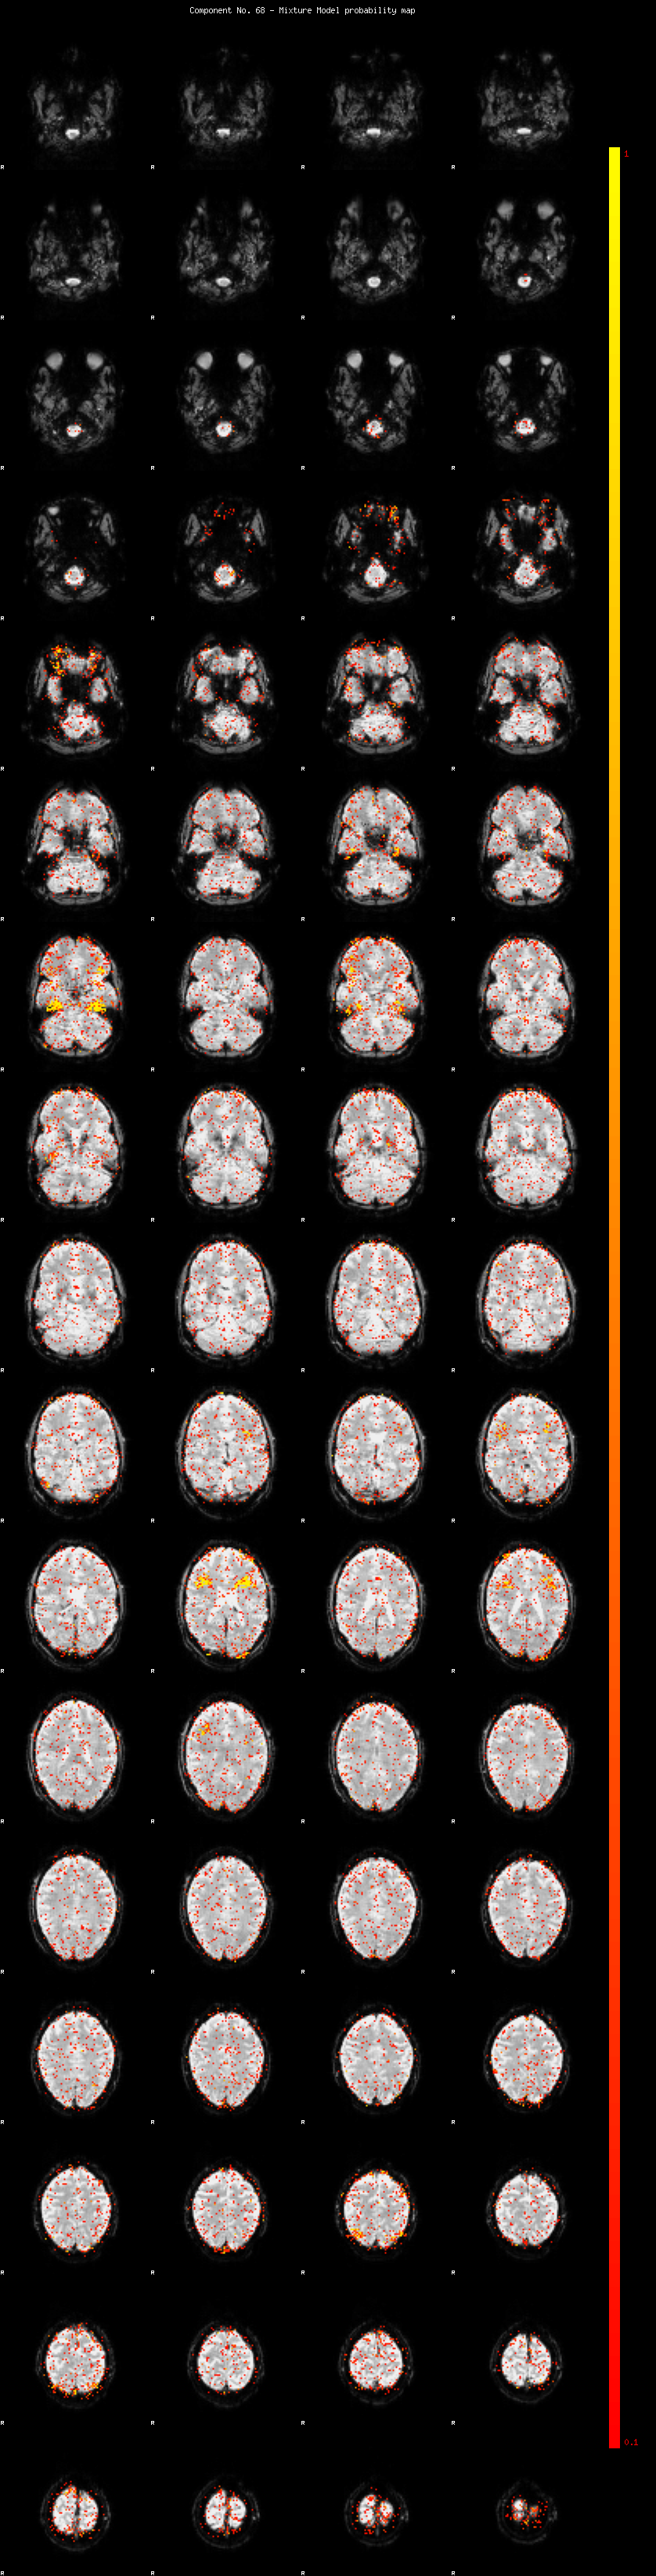

IC_68 Mixture Model fit

Means : 0.000000 2.115673 -2.155012

Vars : 1.000000 1.004480 1.117304

Prop. : 0.961651 0.020989 0.017360